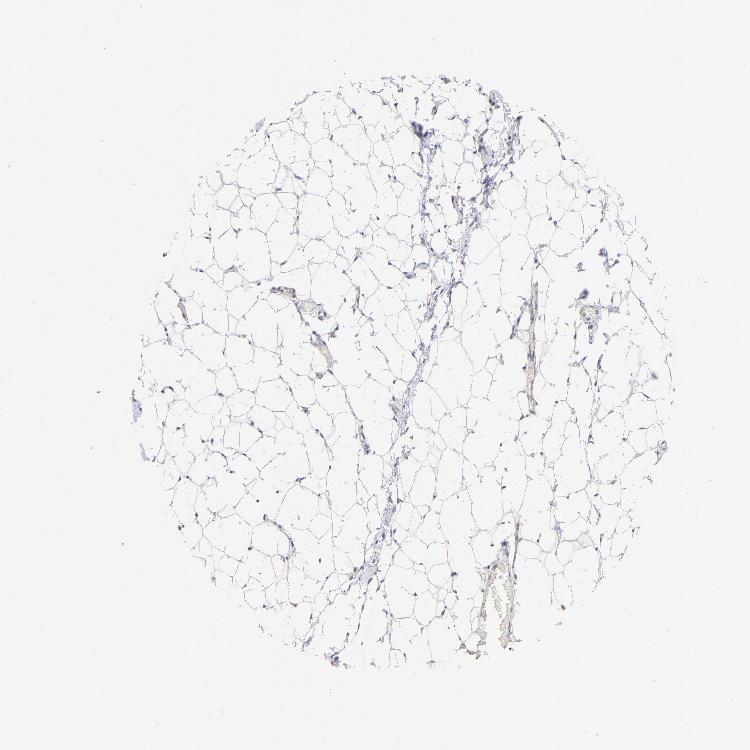

TISSUE PRIMARY DATA SOFT TISSUE Show tissue menu

SOFT TISSUE - Expression summary

SOFT TISSUE 1 - Antibody stainingi

Antibody staining in the annotated cell types in the current human tissue is reported as not detected, low, medium, or high, based on conventional immunohistochemistry profiling in selected tissues. This score is based on the combination of the staining intensity and fraction of stained cells.

Each image is clickable and will lead to virtual microscopy that enables deeper exploration of all samples and also displays staining intensity scores, fraction scores and subcellular localization as well as patient and tissue information for each sample.

Antibody HPA002694Antibody CAB005876

Chondrocytes Not detected-

Fibroblasts Not detectedNot detected

Peripheral nerve Not detectedNot detected